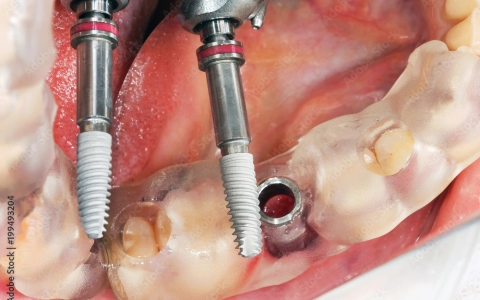

Rehberli İmplant Cerrahisi Tedavisi

Rehberli implant cerrahisi, dijital planlama ve kişiye özel cerrahi guide ile kısa sürede, daha az ağrı, yüksek estetik başarı ve konfor sağlar.